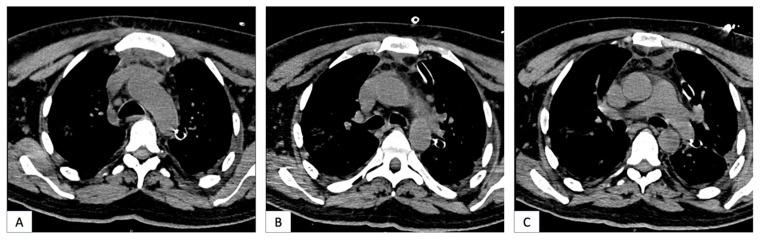

Descending necrotizing mediastinitis (DNM) is a life-threatening condition, generally caused by downward dissemination of oropharyngeal infections through cervical fascial planes. Mediastinal drainage is conventionally achieved by thoracotomy, but a Video-Assisted Thoracoscopic Surgery (VATS) approach is gaining interest due to the reduced invasiveness of procedure. We aimed to evaluate the effectiveness of VATS treatment in patients with DNM. We conducted a retrospective multicenter study including patients with descending mediastinitis that underwent mediastinal drainage through VATS (VATS group) or thoracotomy (thoracotomy group), both in association with cervical drainage. Patients with mediastinitis secondary to cardiac, pulmonary, or esophageal surgery were excluded. The intergroup differences regarding surgical outcome and postoperative morbidity and mortality were compared. A total of 21 patients were treated for descending mediastinitis during the study period. Cervicotomy and thoracotomy were performed in 15 patients (71%), while cervicotomy and VATS were performed in 6 patients (29%). There were no significant differences in surgical outcome, postoperative morbidity, and mortality between groups. VATS treatment was not associated with a higher complication rate. Patients in the VATS group had a shorter operative time ( = 0.016) and shorter ICU stay ( = 0.026). VATS treatment of DNM is safe and effective. The comparison with thoracotomy showed no significant differences in postoperative morbidity and mortality. The VATS approach is associated with a shorter operative time and ICU stay than thoracotomy.

下行性坏死性纵隔炎(DNM)是一种危及生命的疾病,通常由口咽感染通过颈部筋膜平面向下扩散引起。传统上,纵隔引流通过开胸手术完成,但由于该手术的侵入性较小,电视辅助胸腔镜手术(VATS)方法越来越受到关注。我们旨在评估VATS治疗DNM患者的有效性。我们进行了一项回顾性多中心研究,纳入了通过VATS(VATS组)或开胸手术(开胸手术组)进行纵隔引流的下行性纵隔炎患者,两者均联合颈部引流。排除继发于心脏、肺部或食管手术的纵隔炎患者。比较了两组在手术结果、术后发病率和死亡率方面的差异。在研究期间,共有21例患者接受了下行性纵隔炎的治疗。15例患者(71%)进行了颈部切开术和开胸手术,而6例患者(29%)进行了颈部切开术和VATS。两组在手术结果、术后发病率和死亡率方面无显著差异。VATS治疗与较高的并发症发生率无关。VATS组患者的手术时间较短( = 0.016),重症监护病房(ICU)住院时间较短( = 0.026)。VATS治疗DNM是安全有效的。与开胸手术相比,术后发病率和死亡率无显著差异。VATS方法与开胸手术相比,手术时间和ICU住院时间更短。